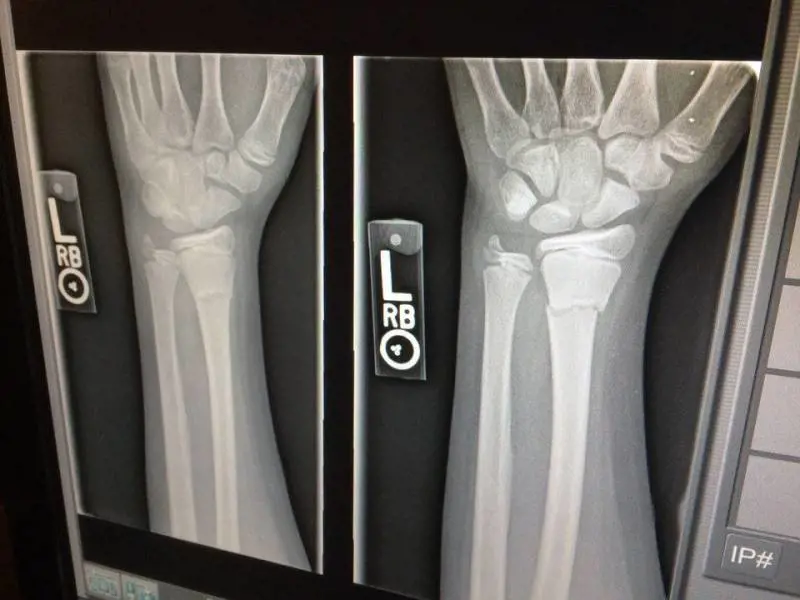

Uno studio tutto italiano mette in correlazione l'ansia con la densità ossea rivelando che le donne in menopausa che soffrono di tale tipologia di disturbo possono avere le ossa più fragili. Si andrebbe così ad aumentare il rischio di fratture, ma potrebbe esserci una soluzione da mettere in atto.

Nelle donne in menopausa affette di disturbi d'ansia vi sarebbe un 4% in più di possibilità di contrarre una frattura alle ossa in un arco di tempo relativo a 10 anni. Questo perché sono stati riscontrati in loro livelli minimi di vitamina D, che compromettono la mineralizzazione ossea, favorendo l'insorgenza di varie malattie. Secondo quanto spiegato dal dottor Catalano, è la prima volta che un team medico riscontra una sorta di legame tra gli stati d'ansia e la salute delle ossa.